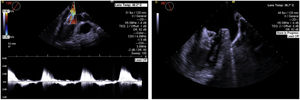

Procedure protocolTo characterize the anatomy and morphology of the LAA and to exclude the presence of thrombus, all patients underwent a cardiac computed angiography (CTA) (example in Figure 1) imaging assessment 48 hours before the procedure or TEE with conscious sedation in the cath lab immediately before LAAO, when CTA imaging was not available.

We used the following ICE imaging protocol for LAAO (example images in Figure 3):

The probe is placed in the mid right atrium with clockwise rotation and posterior tilt to better visualize the fossa ovalis and to guide transseptal puncture in an inferoposterior position. In this view, the LAA is visualized in far field to ensure alignment in the anteroposterior plane and direction of puncture toward the LAA.

The transseptal puncture is enlarged with the LAAO device delivery sheath to facilitate the passage of the ICE catheter to the left through the same orifice.

The ICE catheter is placed parallel to the LAO with posterior tilt to guide device delivery. This position is used to guide the LAAO device landing zone with the LAA, assess correct positioning and stability before release, rule out significant peridevice leaks and monitor for possible embolization.

Finally, after LAAO, the probe is retracted to the right side of the heart and is placed in the right ventricle to exclude pericardial effusion.

Fluoroscopic images of the intracardiac echocardiography probe (black arrows) and its respective echographic images during a left atrial appendage (LAA) occlusion (LAAO) procedure, showing its utility in guiding transseptal puncture (A and B); device deployment (C and D); assessment of device position, significant peridevice leaks using color Doppler and embolization risk (E and F) and exclusion of pericardial effusion (G and H). IAS: interatrial septum.